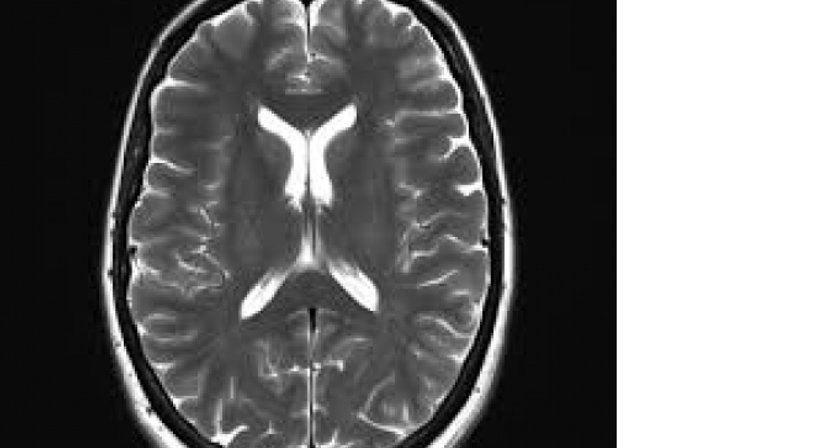

Die Magnetresonanztomographie funktioniert auf der Basis von elektromagnetischen Impulsen (ähnlich den herkömmlichen Radiowellen). Durch diese werden im Körper befindliche Wasserstoffkerne, die in den verschiedenen Geweben unterschiedlich dicht anzutreffen sind, zu einer kurzen Bewegung angeregt, die dann wiederum mittels sehr sensibler Sensoren gemessen werden kann. Die gesammelten Daten werden mittels Computer in Schnittbilder umgerechnet.

Die hohen Kosten der Untersuchung wird durch eine herausragende Bildqualität und einen hohen diagnostischen Wert gerechtfertigt. Durch die Verabreichung von speziellem Kontrastmittel kann die Aussagekraft der Untersuchung noch gesteigert werden. Besonders im neurologischen Bereich, also zur Beurteilung des Gehirnes, ist diese Methode unübertroffen, im Brustraum aber liefert beispielsweise die CT mehr Information.